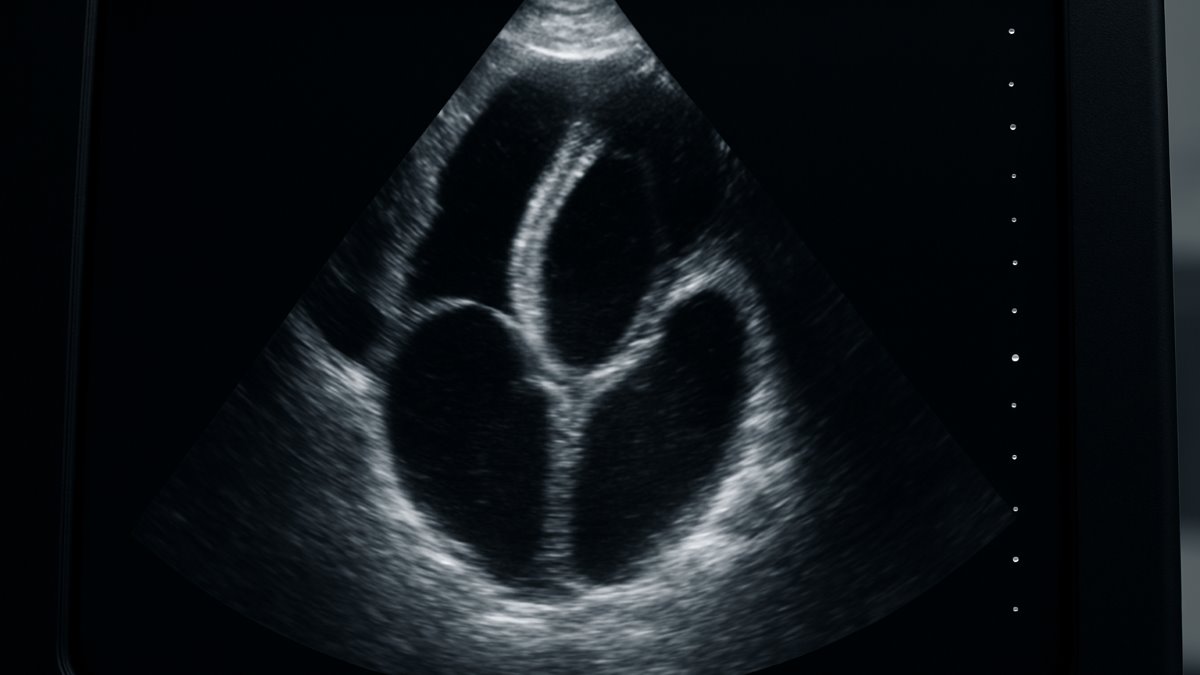

The Role of Nurse Social Support in Hospital Readmission in Patients With Heart Failure: A Cross-Sectional Study Publisher

Summary: Research shows nurse support reduces heart failure readmissions, with unemployment and age also key factors. #HeartFailure #NursingCare

Background and Aims: Hospitalizations and hospital readmissions account for 75%–80% of the economic burden related to heart failure (HF). This study aims to determine the relationship between perceived social support from nurses and hospital readmission rates in HF patients and to identify potential factors associated with hospital readmission, including sociodemographic and clinical variables, perceived social support, and country. Method: We recruited 380 HF patients from two countries (Iceland 92 and Iran 288) from October 2018 to May 2020. We used the social support scale of the Family Functioning, Health, and Social Support (FAFHES) questionnaire for data collection. The hospital readmission rates were collected from patients' hospital records. We performed a general linear model (GLM) to explore the significant factors associated with readmission. Results: A total of 125 (33%) patients were readmitted within 6 months. Among them, 17% were readmitted once, 15% were readmitted twice, and 1% were readmitted three times. The strongest factor associated with the hospital readmission rate was perceived social support. Other significant factors included unemployment, age, and country of residence. Conclusion: This study underlines the important role of perceived social support in hospital readmission among HF patients. Our findings may be useful for better tailoring social support for HF patients to reduce hospital readmission. Moreover, it is recommended to investigate the effects of system-related factors, such as the strategy of healthcare systems in managing HF, on hospital readmissions. © 2025 The Author(s). Health Science Reports published by Wiley Periodicals LLC.